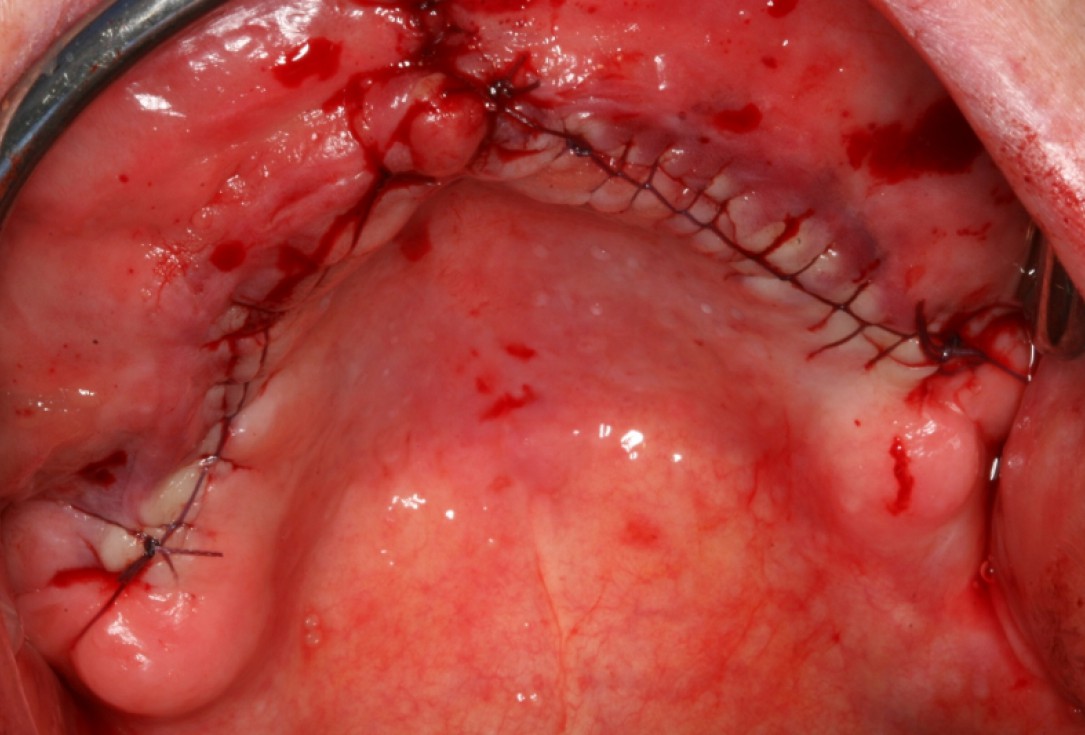

06/10 - Tight wound closure with a continuous seam following the periost splittingCircular bone splitting with maxresorb® & collprotect® membrane - PD Dr. J. Neugebauer